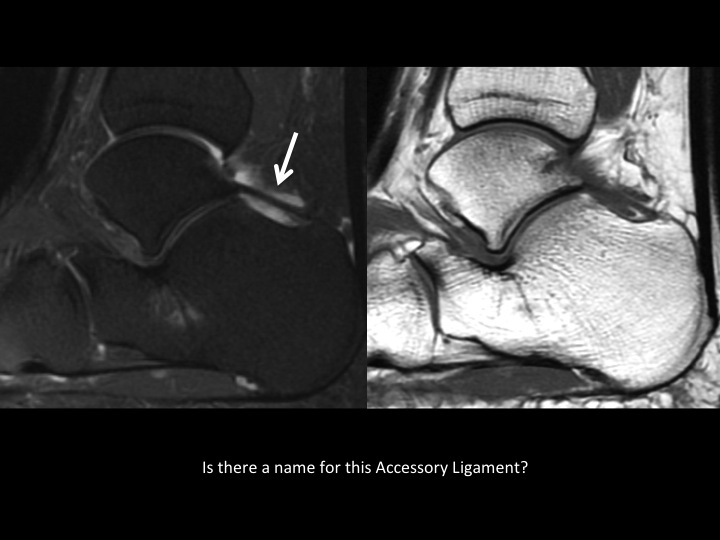

There is an accessory articular facet of the medial talus posterior to the middle facet, with non-osseous extra-articular talocalcaneal coalition (slides 1-2). In slide 3 there is an accessory ligament Ive not seen connecting the lateral tubercle of the posterior talar process and the posterior calcaneal tubercle, with surrounding synovitis (slide 4); does this have a name? As a side question, is there a consensus as to what the cyst-like changes are deep to the angle of Gissane in the calcaneus? Do you all report this? I consider this incidental, does anyone disagree?